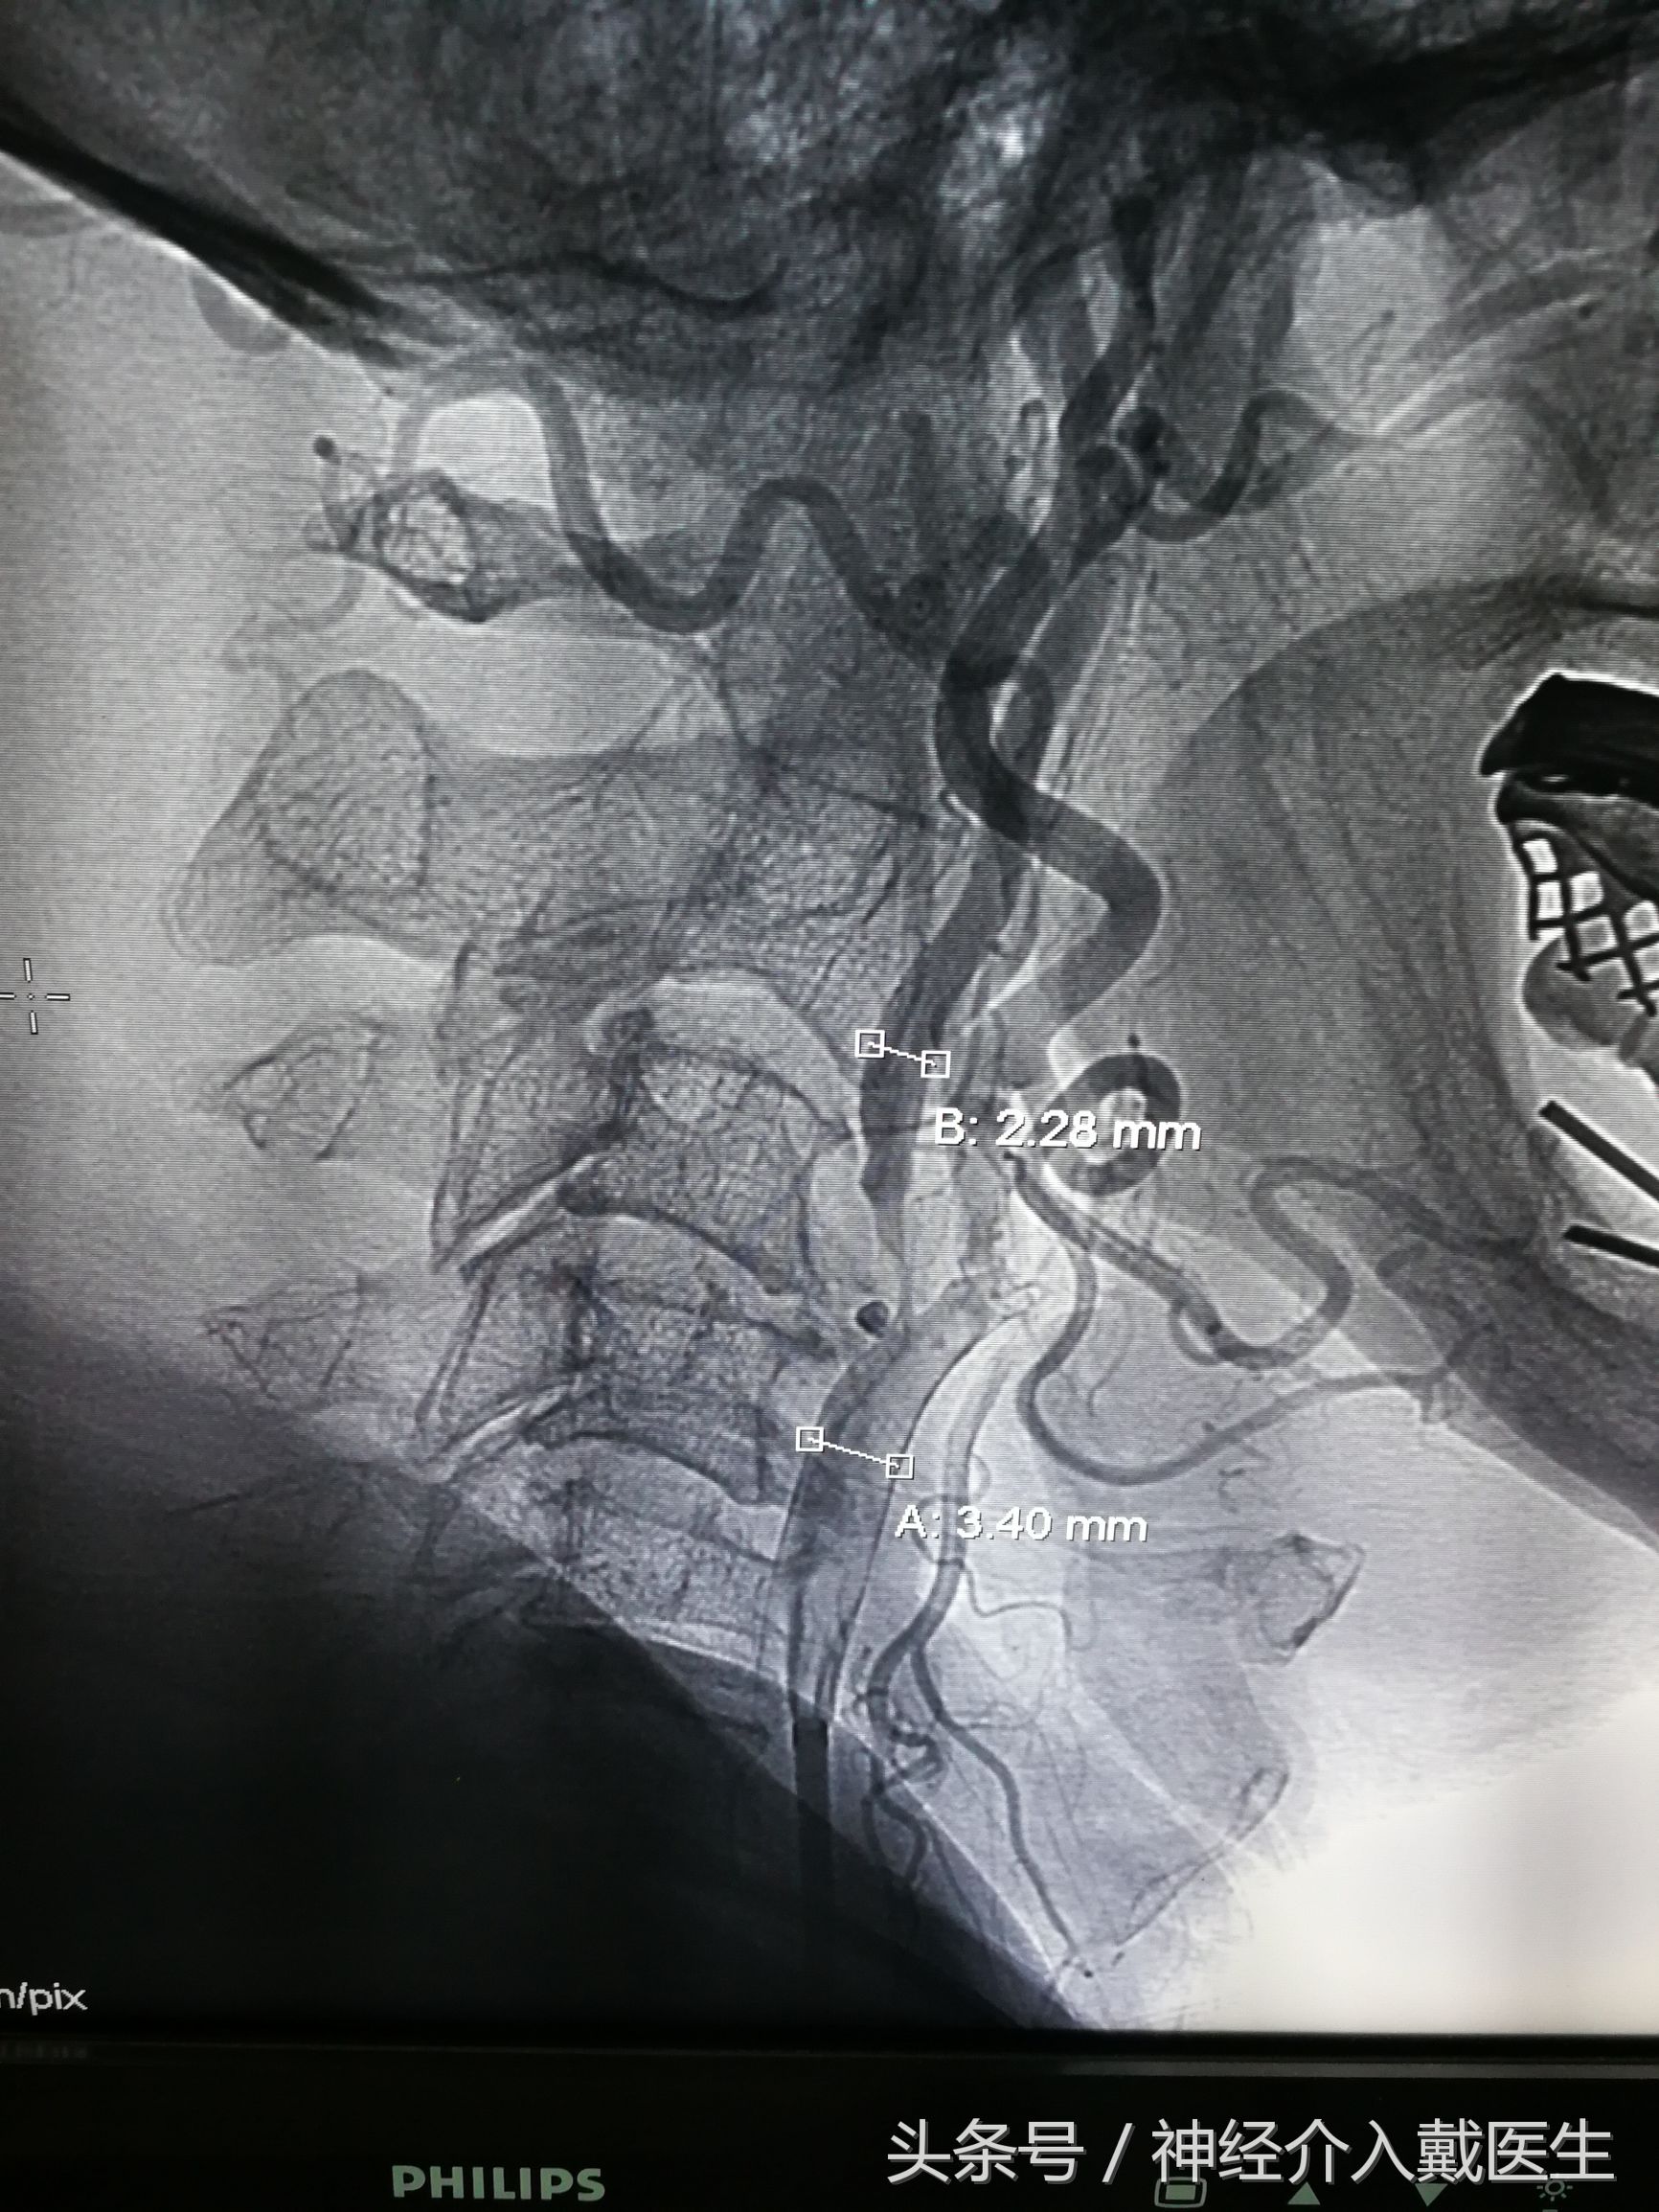

脑血管造影显示颈内动脉狭窄接近90%

不学医的人一看,都知道是蛮狭窄的,经过仔细计算,狭窄达90%,快闭塞了,怎么不晕倒啊?